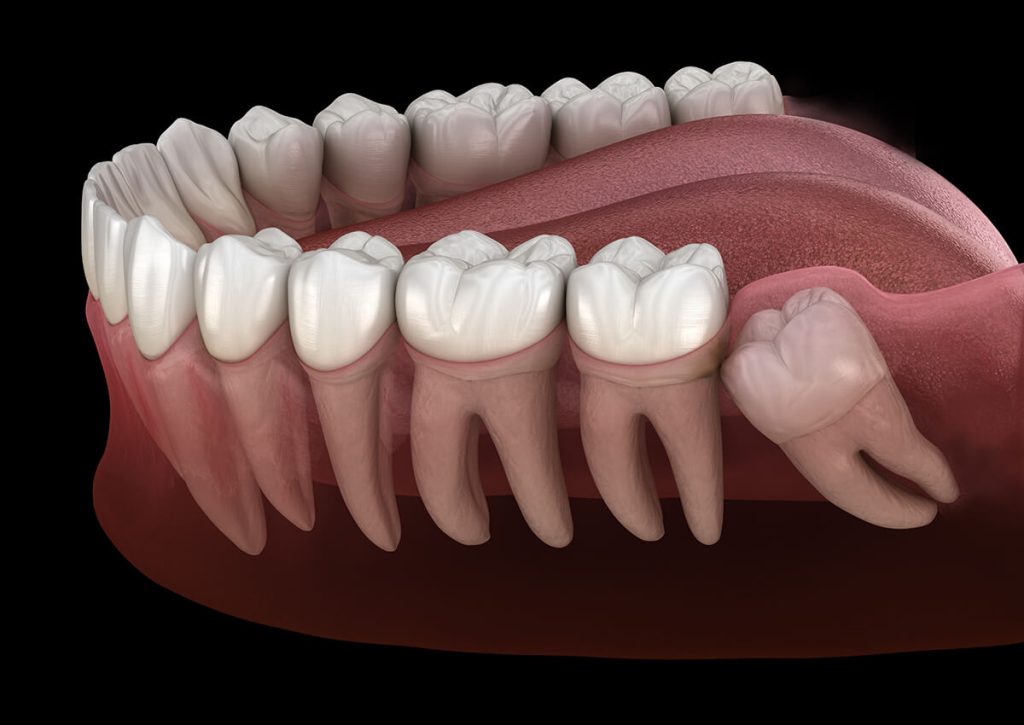

If your mouth lacks space for third molars to fully erupt, several problems can occur. Impacted wisdom teeth should ideally be removed before their roots fully develop. This can occur as early as age 12 or as late as the early twenties. Problems tend to increase after age 30. Reasons for removal include:

Pericoronitis, a localized gum infection, is common when there is not enough room for full eruption. It can cause pain, swelling, and difficulty with chewing or swallowing.

Fluid-filled cysts can develop around impacted teeth, slowly expanding and damaging adjacent bone and teeth. Rarely, tumors may also form.

Wisdom teeth may contribute to crowding, particularly in the lower front teeth, especially after braces.

Inadequate room for cleaning can lead to decay and gum disease in the second molars next to impacted wisdom teeth.

As you age, jaw bone density increases and wisdom tooth removal can be more complex with a longer recovery time. If your wisdom teeth are fully impacted and not causing problems, your surgeon may recommend monitoring them until intervention is necessary.